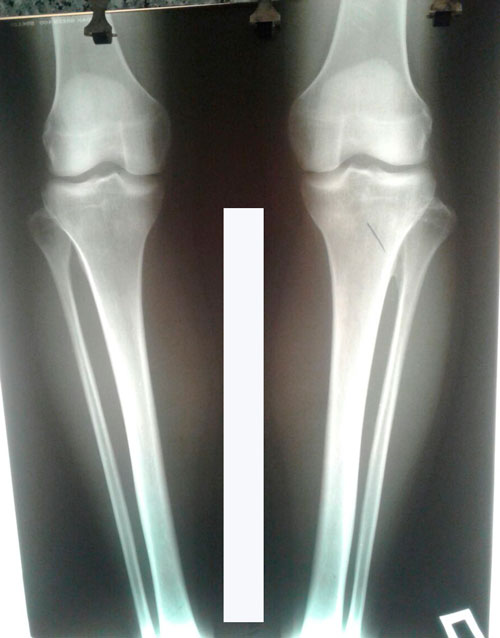

Рентген снимки через 1,5 месяца с момента снятия аппаратов